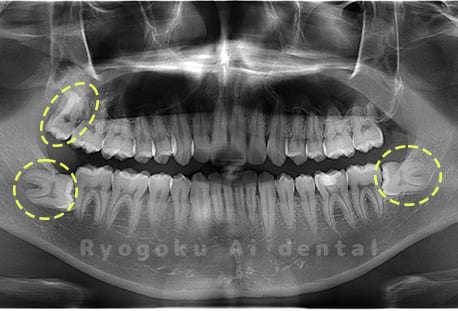

Case04

- 原因

- 上顎の親知らず、下顎の水平埋伏の親知らず

- 治療内容

- 上顎の親知らず、下顎の水平埋伏の親知らずを抜歯したケースです。

<リスク・副作用>

手術後は痛み、腫れ、痺れなどの副作用が生じる場合があります。